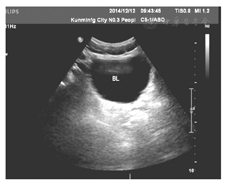

病例2王某,女,71岁,因卵巢癌晚期合并大量腹水于2014年11月25日入院。患者约于1年前被诊断为卵巢癌,行腹腔镜手术(术式不详),经过6次化学药物治疗。于4个月前出现腹腔积液。本次入院主要是因为大量腹水至卧床、呼吸困难,时有腹部疼痛,见图3。入院后的第5日,我们给予腹部穿刺、置入微管持续引流,每日控制引流1 500 ml,引流半月腹水无减少情况,多为渗出性,腹水中有癌细胞检出,患者虚弱。于入院后第20日开始给予三氧水腹腔内灌注引流,每日2次,每次100 ml,灌注后闭管2 h后开放引流。3 d后引流量开始减少,连续7 d后,每日开放引流,24 h腹水量减少至200 ml,渗出液中癌细胞数、红细胞数明显减少。于引流后第9日患者夜间活动时引流管脱落,未再引流。隔日复查B型超声仅为少量腹腔液体,好转出院,见图4、图5。